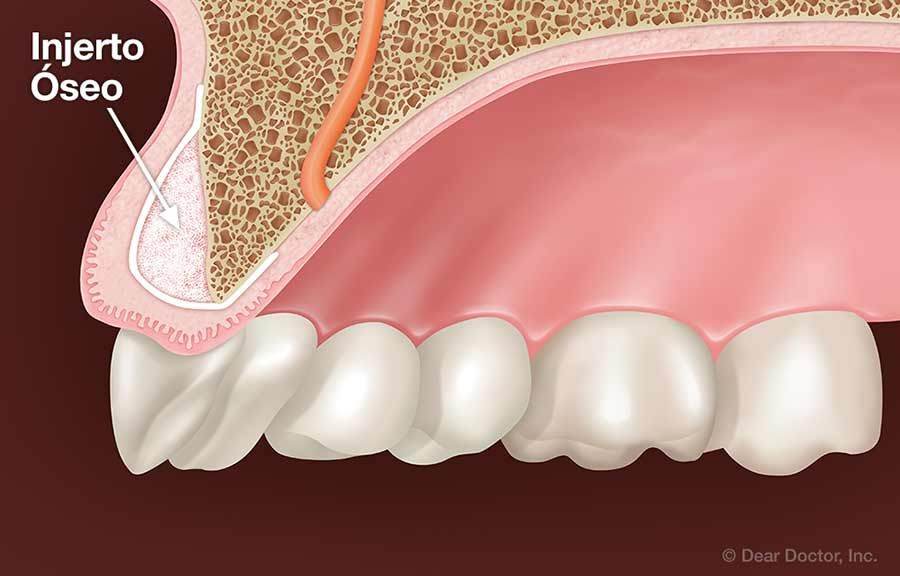

Se trata de un procedimiento quirúrgico mediante el cual colocamos material óseo (natural o sintético) en una zona donde hay pérdida o deficiencia de hueso. Este “material de refuerzo” actúa como un andamio que permite al organismo regenerar hueso nuevo en esa área específica. Es decir, nos ayuda a restaurar estructura, volumen y soporte óseo, sobre todo en la mandíbula y el maxilar.

En odontología, el injerto óseo es fundamental cuando queremos colocar un implante dental pero no existe suficiente hueso para sostenerlo de manera estable. También es útil después de una extracción dental, para prevenir que el hueso se reabsorba, o en casos donde hay enfermedades como la periodontitis que han deteriorado la base ósea.

Cuando el hueso que rodea la raíz del diente se deteriora, el diente pierde estabilidad y comienza a “aflojarse”. En estos casos, el injerto de hueso dental puede ser una solución efectiva para regenerar el tejido óseo perdido y fortalecer la base que mantiene los dientes firmes en su lugar.

Hueso colapsado o deprimido por reabsorción ósea

Cuando el hueso ha perdido volumen, se ve “hundido”, delgado o colapsado. Esto es común después de muchos años sin dientes, o cuando hay infecciones o inflamación crónica no tratada.

Aquí, el injerto óseo cumple un papel estético y funcional: recuperamos el contorno del hueso, restauramos el soporte facial y permitimos futuros tratamientos como implantes o prótesis fijas.